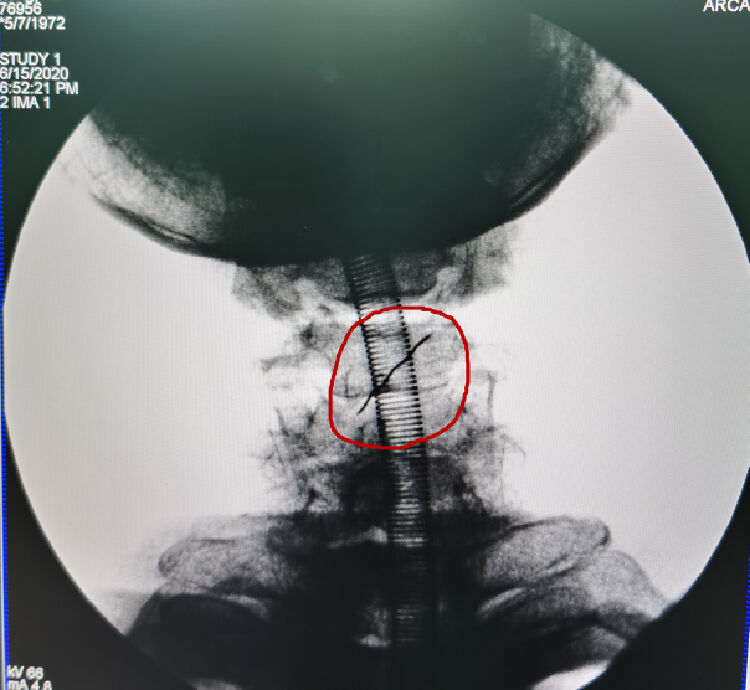

张先生又赶到南方医科大学深圳医院急诊科就诊,第一时间,消化内科和耳鼻喉科的医生想通过胃镜或者食管镜取出。然而,异物很狡猾,镜子根本看不到,只能看到两处破损。术中的X光线显示,异物仍然在食管入口平面,只是它不露面,镜子就没法把它拽出来。而且,咽部要道两边都是大血管——颈总动脉和颈内动脉,伤到哪条都会出人命。

在DSA室里,在射线的透视下,胸外科张建华主任团队寻找着金属异物的位置——在食管和脊柱之间的间隙里。此时,胸外科还想努力一下,用微创的方法取出来。但异物的两头尖锐、光滑,医生尝试用穿刺针都套不住,因为它是不规则形状,两头尖,中间还有螺纹,胸外科医生们好不容易用穿刺针把它套住了,往外一拽,又掉了!